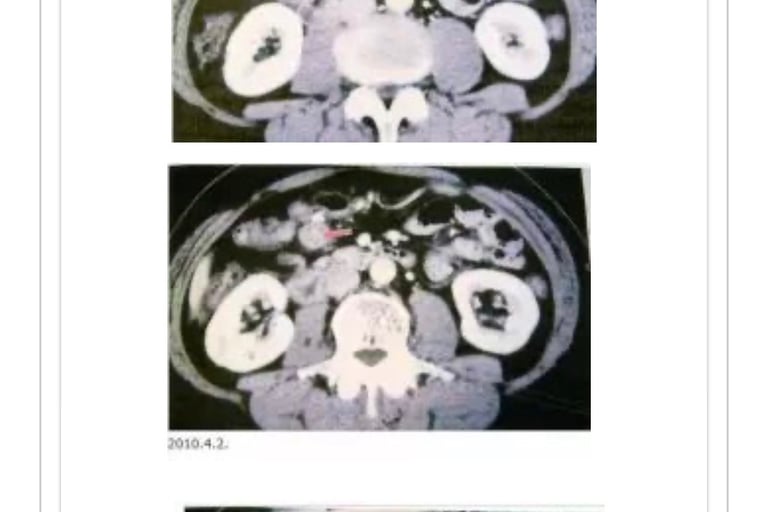

K・S(1939年生、男性)

2004年10月、诊断为胃癌。05年2月7日胃切除、脾脏附近淋巴切除。病理分析结果为中分化腺癌,有高度淋巴管浸润和轻度静脉浸润。05年5月19日来我院就诊,因为口服抗癌剂TS1致使肝功能恶化,服药停止。

共振反应显示肺部至肚脐但范围伴随胰腺癌反应。至9月12日合计MW照射29次。06年9月29日的CT检查结果为早期胰腺癌(照片1)。肝脏、胰腺、大肠均有汞反应,服用活性炭。未发现病原性大肠杆菌和肉毒杆菌感染。远红外线温热仪器治疗和MW照射结合,至06年10月23日MW照射

合计33次。癌症活性反应消失。11月15日CT检测胰腺癌阴影消失(照片2)。前期治疗医师承认针对患者有误诊。至12年2月。近7年患者恢复正常生活。